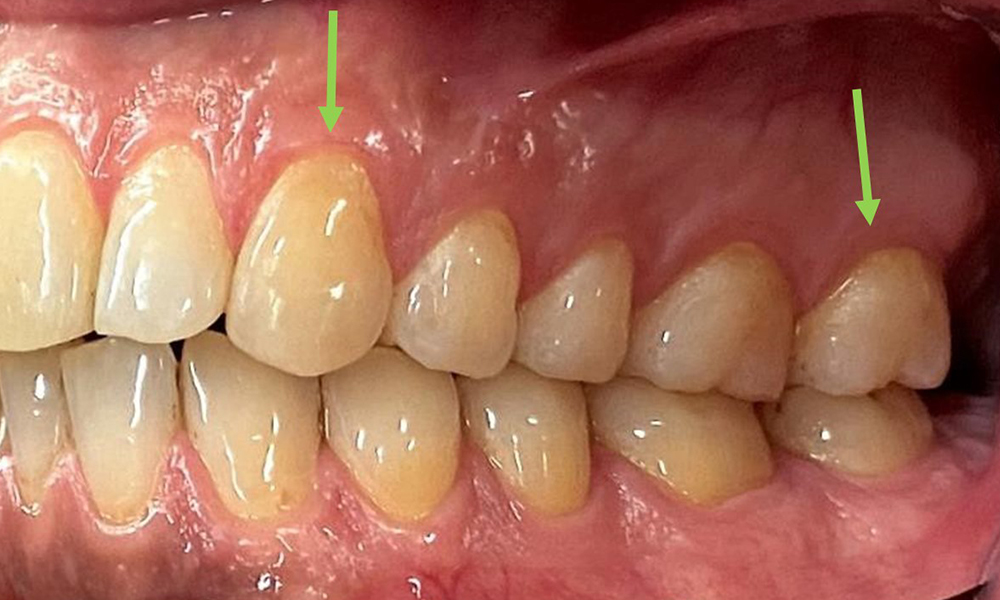

There were no pathological extraoral findings. During intraoral examination, inspection of the frontal view revealed brownish discolouration near the keratinised gingiva and at the transition to the moveable mucosa (Fig. 2), which could be attributed to nicotine consumption. Whitish mucosal lesions were observed on the palate, particularly near the maxillary molar palatal surfaces, indicating increased keratinisation and can also be attributed to nicotine consumption. The tongue was covered with a removable white and brownish coating.

The patient has full dentition with a total of 28 teeth. There were noteworthy erosions and attritions. (Fig. 4, Fig. 5). Due to bruxism, the patient has been wearing a splint with an adjusted bite block at night for many years. The erosions were caused by long-term consumption of isotonic beverages. No periodontal bone loss or active caries were observed.

At 1 to 3 mm, the clinical probing depths were within the physiological range. Maxillary recessions of up to 1 mm were observed from 13 to 16 and 23 to 27. The BOP was 15%.